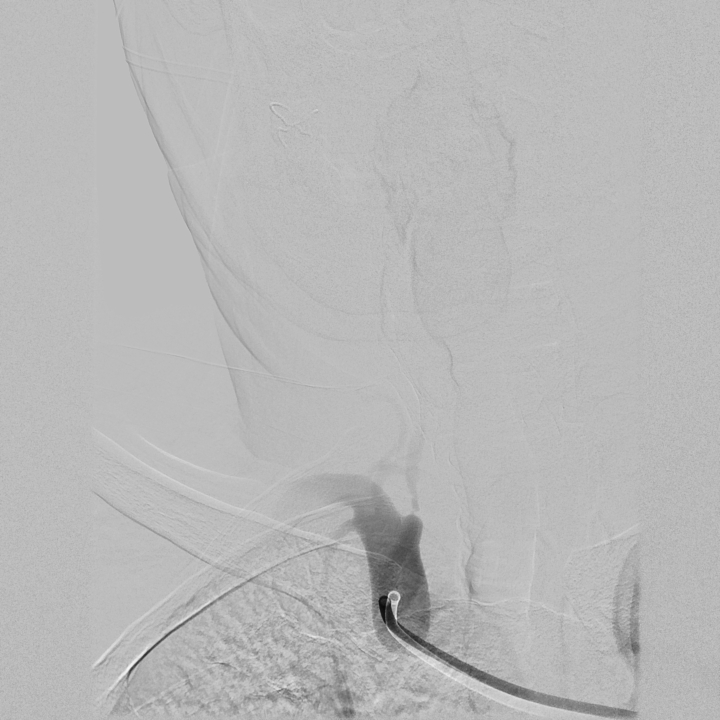

血栓后綜合征介入治療

治療前

治療后

顯著改善患者生活質(zhì)量,本技術(shù)省內(nèi)領(lǐng)先。